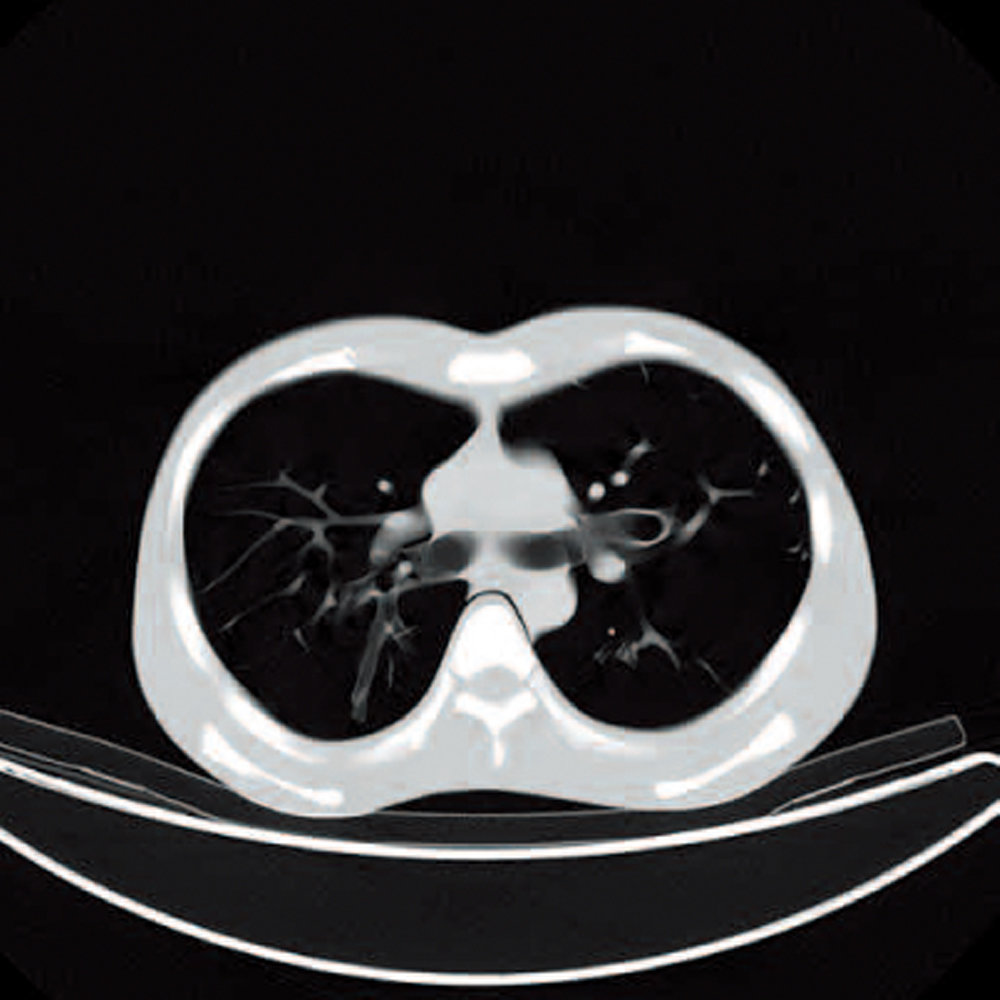

CT Whole Body Phantom - With Pathologies

1A unique, life size whole body phantom for CT provides a variety of educational application as well as visual evaluation in finding out optimal scanning conditions

| Training skills / Applications | Plain X-ray / CT /Basic patient positioning |

| Case / Pathology | Refer to PDF( Anatomy and Pathologies) |